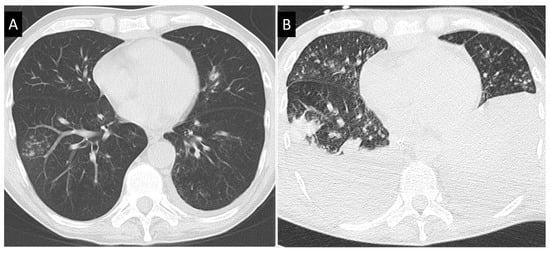

- Greene, R.E.; Schlamm, H.T.; Oestmann, J.-W.; Stark, P.; Durand, C.; Lortholary, O.; Wingard, J.R.; Herbrecht, R.; Ribaud, P.; Patterson, T.F.; et al. Imaging findings in acute invasive pulmonary aspergillosis: Clinical significance of the halo sign. Clin. Infect. Dis. 2007, 44, 373–379. [Google Scholar] [CrossRef]

- Prasad, A.; Agarwal, K.; Deepak, D.; Atwal, S.S. Pulmonary aspergillosis: What CT can offer before it is too late! J. Clin. Diagn. Res. 2016, 10, TE01–TE05. [Google Scholar] [CrossRef]

- Munoz, P.; Vena, A.; Cerón, I.; Valerio, M.; Palomo, J.; Guinea, J.; Escribano, P.; Martínez-Sellés, M.; Bouza, E.; Promulga Project Group. Invasive pulmonary aspergillosis in heart transplant recipients: Two radiologic patterns with a different prognosis. J. Heart Lung Transplant. 2014, 33, 1034–1040. [Google Scholar] [CrossRef]

- Herbrecht, R.; Guffroy, B.; Danion, F.; Venkatasamy, A.; Simand, C.; LeDoux, M.-P. Validation by real-life data of the new radiological criteria of the revised and updated consensus definition for invasive fungal diseases. Clin. Infect. Dis. 2020, 71, 2773–2774. [Google Scholar] [CrossRef]

- Jin, J.; Wu, D.; Liu, Y.; Pan, S.; Yan, J.L.; Aram, J.A.; Lou, Y.-J.; Meng, H.; Chen, X.; Zhang, X.; et al. Utility of CT assessment in hematology patients with invasive aspergillosis: A post-hoc analysis of phase 3 data. BMC Infect. Dis. 2019, 19, 471. [Google Scholar] [CrossRef]